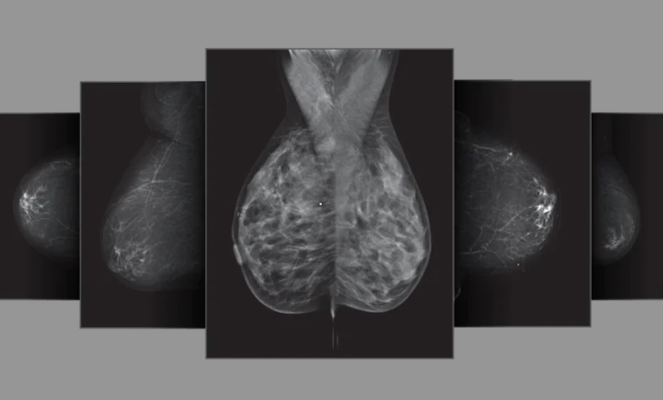

Densitas offers a robust and comprehensive mammography quality assurance platform, comprised of intelliMammo and intelliMaven. IntelliMammo is built on deep learning and machine learning algorithms that assess clinical image quality and breast density that are the foundation for advanced analytics, continuous quality control, efficient workflows and remote quality oversight. In an industry-first move, intelliMaven is a GPT AI application engineered to streamline workflows, deliver on-demand expert feedback, and foster a culture of confidence and autonomy among technologists. The integrated platform delivers a scalable, sustainable quality assurance system tailored for mammography facilities to maximize operational efficiency, optimize compliance with the FDA Mammography Quality Standards Act (MQSA) EQUIP, and meet ACR accreditation standards. The platform empowers facilities to maximize resource allocation and focus on activities that drive the most value.

With iCAD’s AI-enabled ProFound Breast Health Suite, offering clinically proven solutions for cancer detection, density assessment, and personalized risk evaluation, medical professionals will have a more well-rounded set of data on each patient’s breast health. Clinical studies have demonstrated that the use of iCAD’s ProFound AI solutions can significantly improve reading sensitivity and specificity and reduce reading times, thus enhancing clinical decision support and workflow efficiency for radiologists.

ProFound AI offers clinically proven time-saving benefits to radiologists, including reducing reading time by 52.7%, thereby halving the time it takes radiologists to read 3D mammography datasets. ProFound AI for DBT improved radiologist sensitivity by 8% and reduced unnecessary patient recall rates by 7.2%.i The ProFound Riskii platform has a proven track record of predicting the risk of breast cancer 2.4x more accurately in the next year than traditional lifetime risk models.iii,iv iCAD’s ProFound Density Assessment uses mammography images to categorize breast density, leading to personalized patient care plans with supplemental screenings and a custom schedule.

IntelliMammo reduces clinical image quality error rates by as much as 44%,v and streamlines compliance with key MQSA EQUIP and adherence to ACR accreditation requirements, quality assurance and oversight tasks in mere seconds and minutes, as opposed to days and weeks. IntelliMaven is designed to increase radiological technologists’ clinical confidence and autonomy, and to limit interruptions to radiologists when reading exams. IntelliMammo densityAI breast density has been clinically validated to have a strong association with breast cancer risk, providing a practical automated method for risk stratification.vi